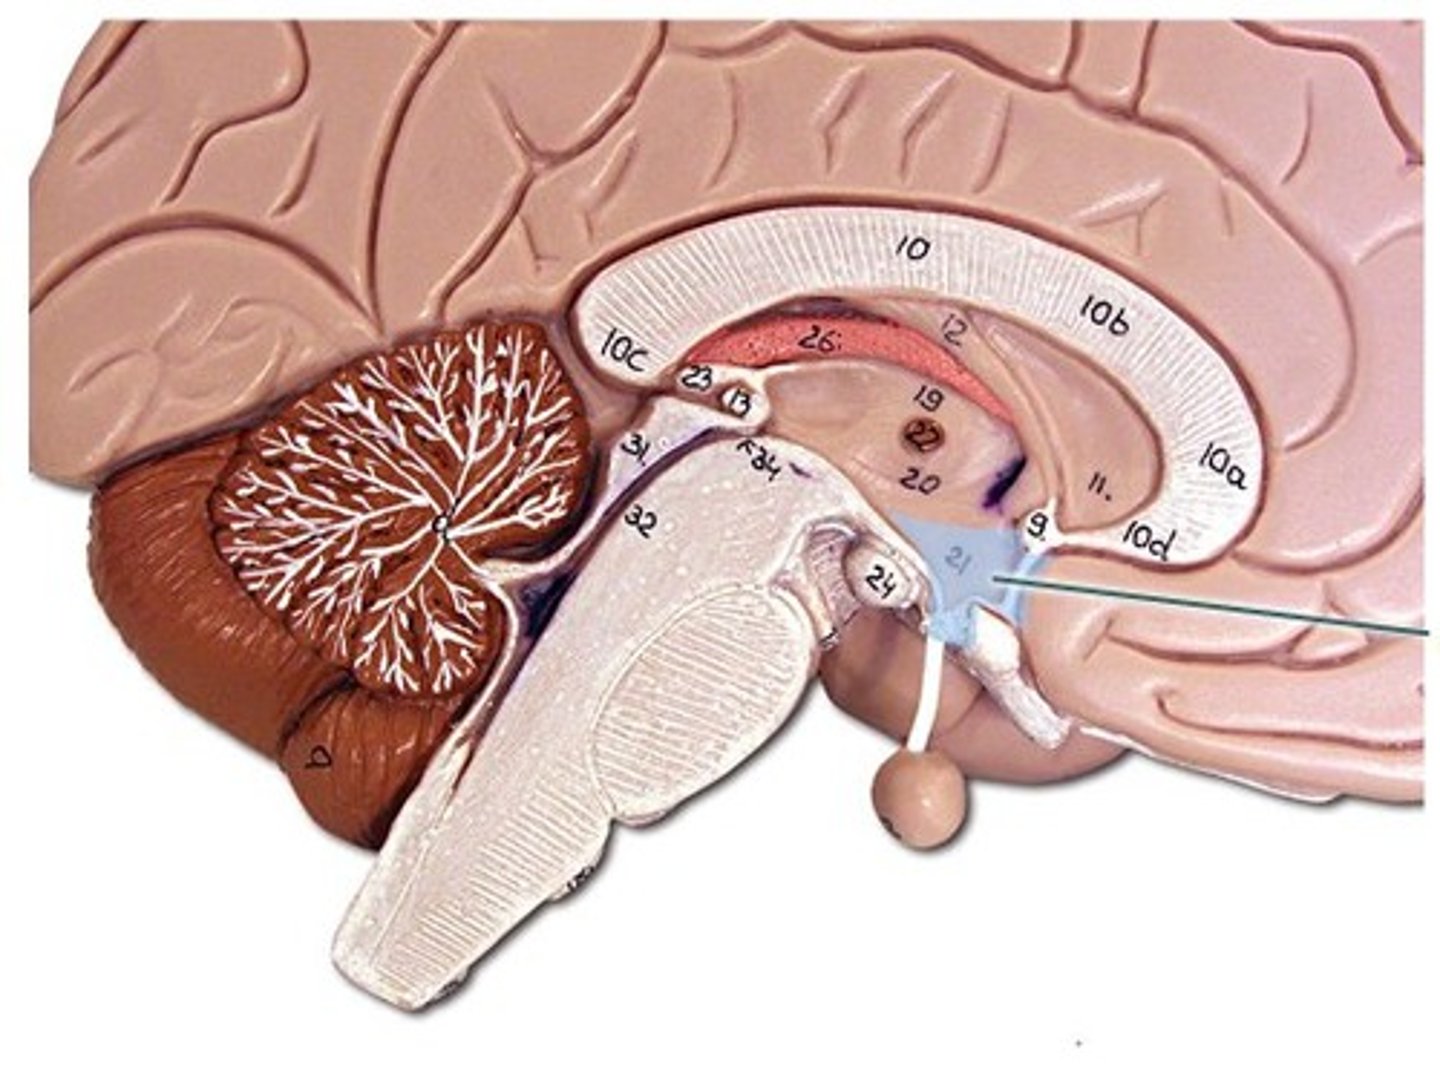

Parts of the brain

- cerebrum

- brain stem

- cerebellum

Parts of the brain: cerebrum

- the bulk of the brain

- made up of the telencephalon and the diencephalon

Diencephalon

- 2nd layer of the cerebrum (deep to the telencephalon)

- the core of the cerebrum, surrounded the bat cerebral hemispheres

- responsible for sensory and motor relay into and out of the brain, as well as control over the autonomic nervous system

parts of diencephalon

thalamus and hypothalamus

- encloses the 3rd ventricle

diencephalon: thalamus

- 2 bodies, 1 per hemisphere

- this part of the brain is responsible for relaying sensory information (except sense of smell) to other areas of the brain

Diencephalon: Hypothalamus

- small structure below the thalamus that is commented to the pituitary gland

- controls the release of hormones through the pituitary gland

Support and Protection of the Brain: Ventricles

- also provides support and protection to the Brain

- made up of 4 hollow spaces that are continuous with each other and the spinal cord

- these spaces contain cerebral spinal fluid

lateral ventricles (2)

third ventricle

fourth ventricle

Ventricles: Lateral Ventricles

- paired "C" shapes spaces deep within the cerebral hemispheres

- a portion of the lateral ventricles can be found in each lobe

Ventricles: Third Ventricle

- 1

- located in the middle of the diencephalon between the 2 halves of the thalamus

- connected to the lateral ventricles by the

interventricular foramina

Ventricles: Fourth ventricle

- sits between the pons/medulla and the cerebellum

- connected to the third ventricle between the cerebral aqueduct

- it is continuous with the central canal of the spinal cord and the subarachnoid mater